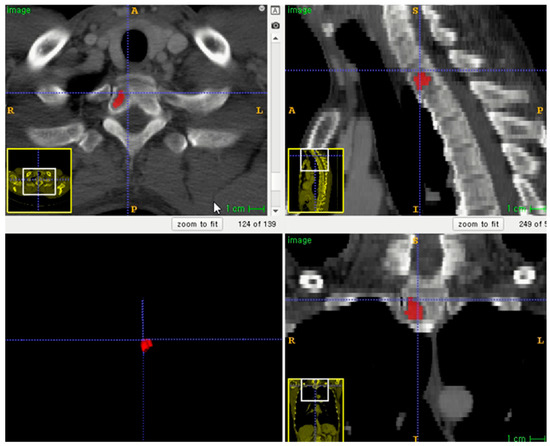

The entire volume of interest (VOI) was manually segmented based on contrast-enhanced CT images. Segmentation was performed using an open-source program (ITK-SNAP software, version 3.8.0, http://www.itksnap.org, accessed on 1 December 2020) (Figure 2) [16]. To correct the variability of voxel size, segmented VOIs were resampled to isometric voxels of 1 mm × 1 mm × 1 mm [17]. The radiomics features of VOI segmentation were extracted using the PyRadiomics package (https://github.com/Radiomics/pyradiomics/, accessed on 10 June 2021) [18]. VOI segmentation was performed by one trained technologist (K.-E.L., with 2 years of experience in medical imaging segmentation). A radiologist (S.-Y.L.) supervised the segmentation.

Figure 2.

Example of lesion segmentation on axial skeleton.